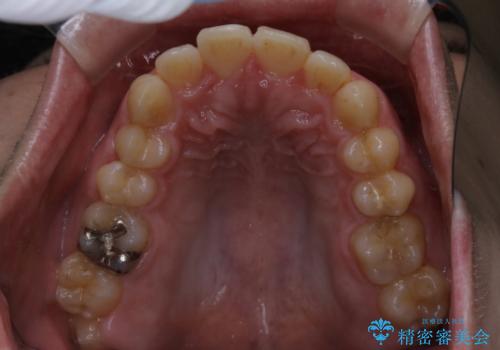

突出感とがたつきの改善を行うために大きなスペースが必要であったため、親知らず以外の歯を4本歯を抜歯する計画を立てました。

もともとの歯の根っこの位置の関係で、治療途中において上下の真ん中の位置がずれてしまいました。機能的には問題ありませんが患者様と相談し、期間を延ばした上で真ん中を合わせる治療を追加で行いました。

今回のように歯を大きく動かす場合、インビザライン治療ではどうしても歯が傾いてしまう場合があります。

ワイヤー治療では歯の傾きを抑えながら大きい距離の移動が可能で、かみ合わせが深くなるリスクも少ないです。